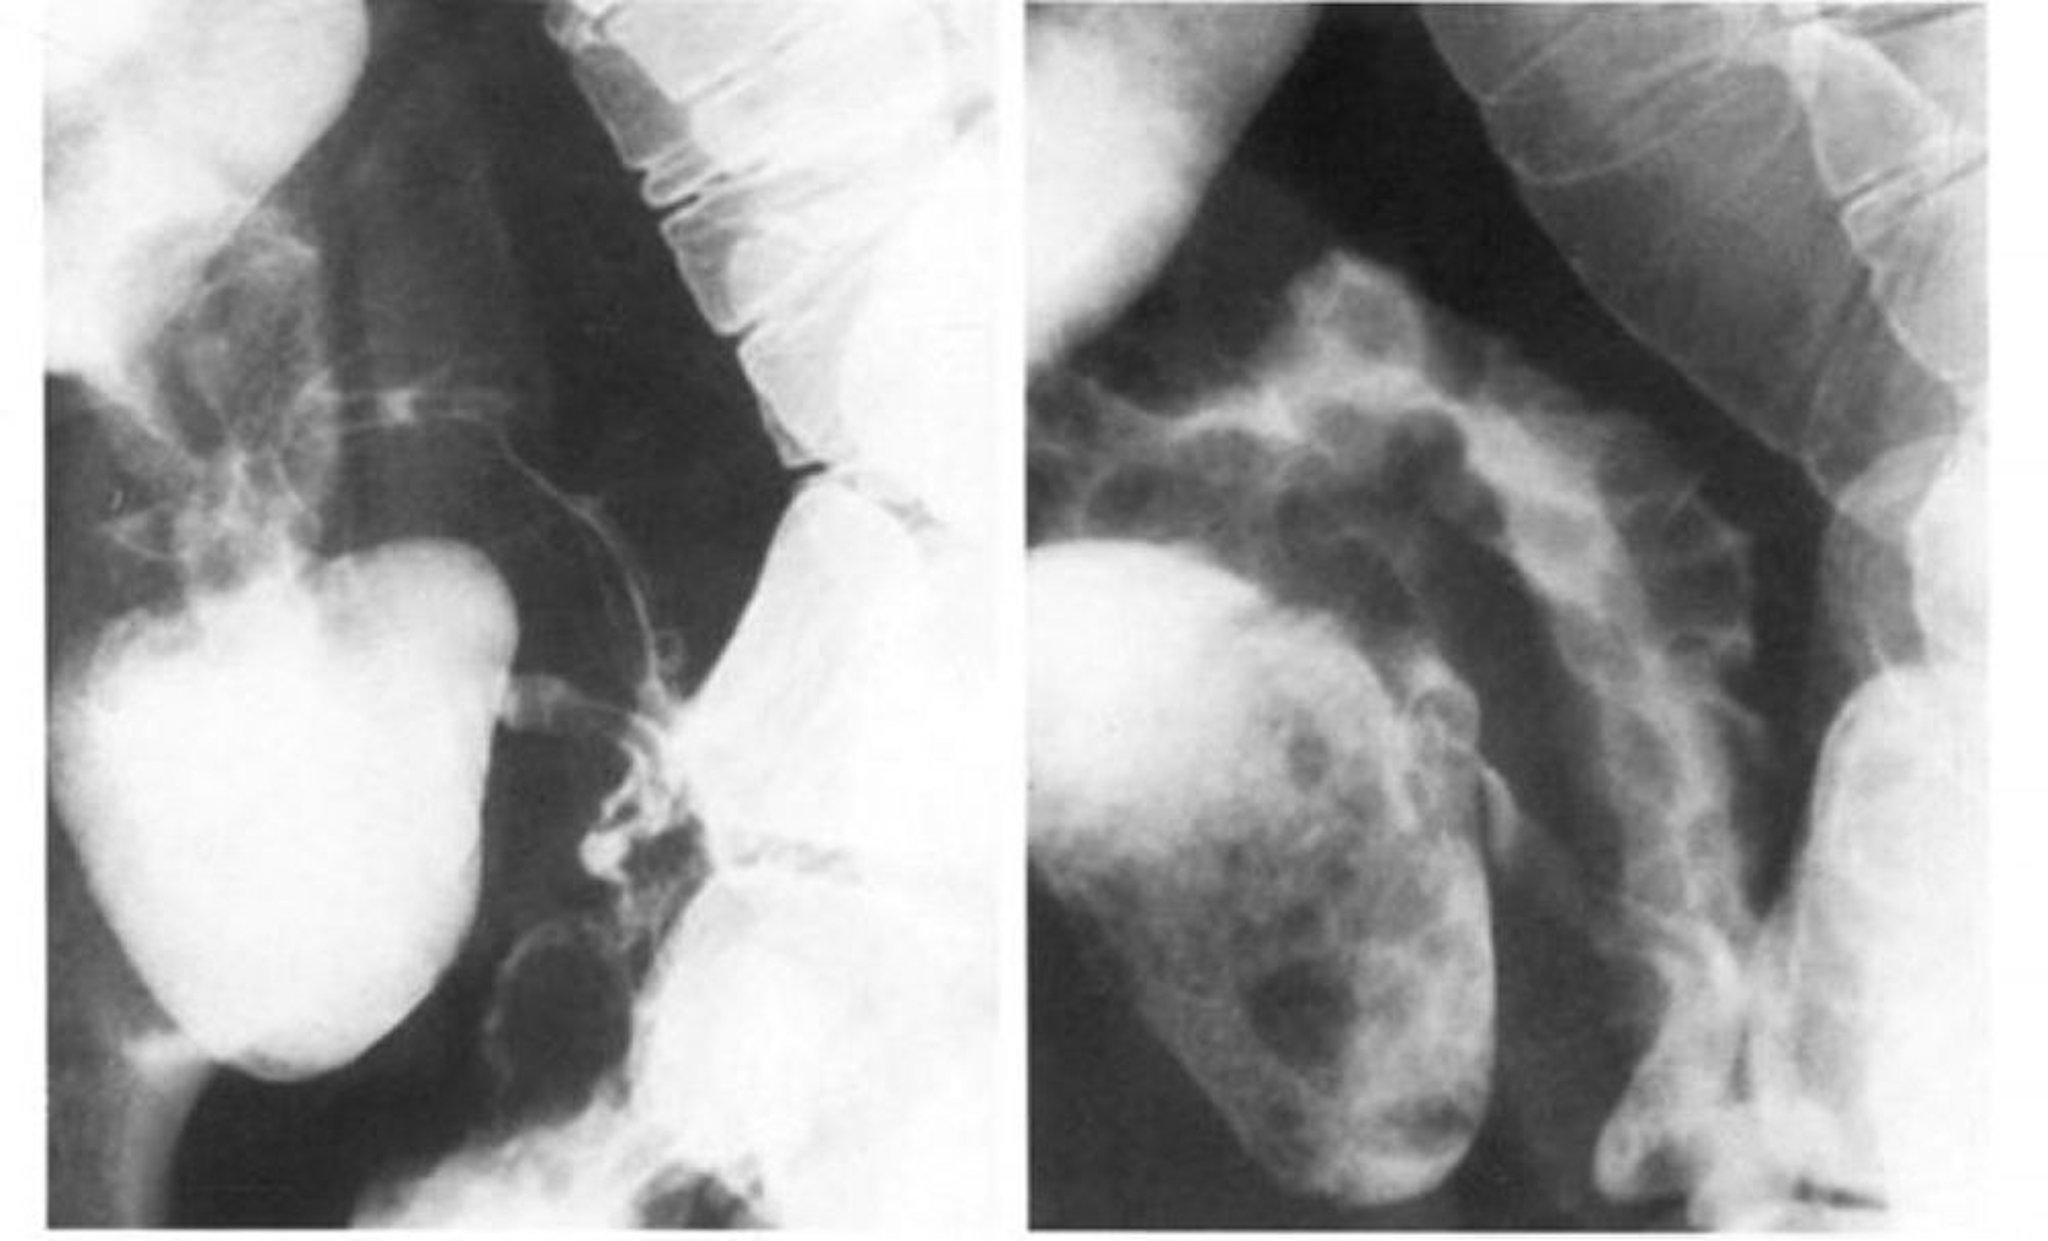

Seguimiento de la enfermedad de Crohn en el intestino delgado que muestra el signo de la cuerda

La imagen de la izquierda muestra que el espasmo oblitera el patrón en empedrado del íleon terminal, que se observa mejor con doble contraste en la imagen de la derecha.